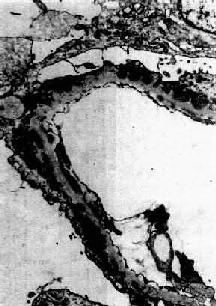

膜性肾小球肾炎

图12-19 膜性肾小球肾炎

电镜下见肾小球毛细血管基底膜增厚,电子致密沉积物被增生的基底膜包围并埋藏于基底膜内